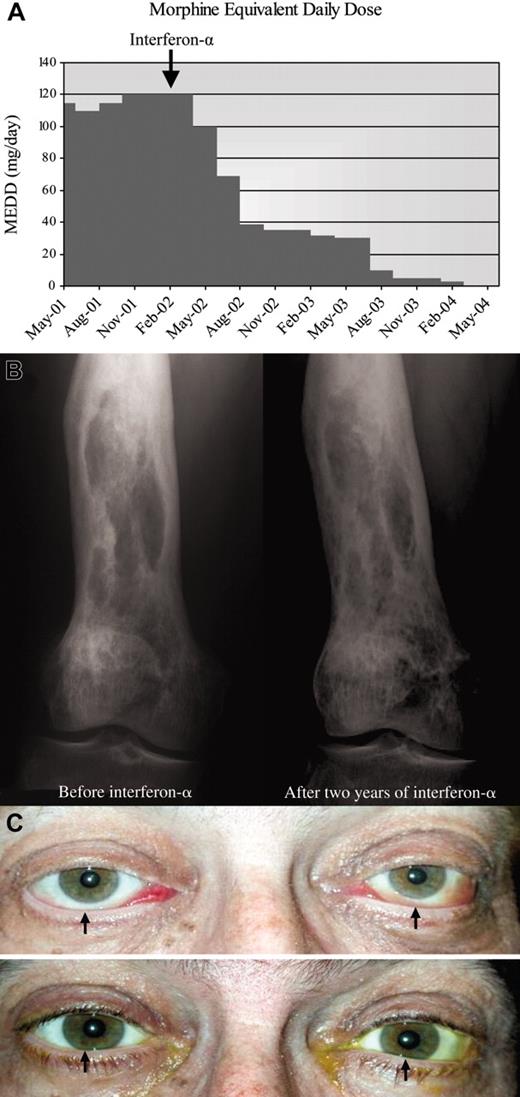

A 58-year-old man was evaluated for ongoing leg pain, treated diabetes insipidus, and panhypopituitarism. The long bone radiographs of his legs showed bilateral osteosclerosis of the diaphyses and metaphyses sparing the epiphyses of the femur and tibia. A right femur bone biopsy revealed infiltration with diffuse large foamy histiocytes, Touton-like giant cells and lymphocytic aggregates and fibrosis diagnostic of Erdheim-Chester disease. 99mTc-MDP bone scan identified multiple long bone lesions as well as T11 thoracic and L3 lumbar vertebral lesions. Unfortunately, neither radiotherapy to his spine and knees nor strontium-90 radionuclide nor high-dose prednisone halted the ongoing progression of his disabling pain syndrome requiring high-dose opioids. Interferon-α, 3 × 106 units subcutaneous 3 times per week, later decreased to 1 × 106 units because of significant fatigue was very well tolerated and allowed tapering down his opioids within 3 months (Figure 2A). After 2.5 years of interferon-α maintenance therapy, he is pain free and off analgesics, and the follow-up tests show significant improvement of the bone radiographs (Figure 2B).

Figure 2.

Response to interferon-α in patients 2 and 3. (A) Morphine equivalent daily dose (MEDD; mg/d) needed to manage pain before and after interferon-α therapy. Patient required 120 mg/d opioids before starting interferon-α. After 2 years, he no longer needs opioids. (B) Bone radiograph of the right femur reveals mixed osteosclerotic and osteolytic lesions before treatment. Ongoing improvement is seen after 2 years of treatment with interferon-α. (C) (Top) Bilateral exophthalmos with chemosis, engorged conjunctival vessels, and inferior scleral show (arrows) at presentation. Loss of eyelashes because of recent chemotherapy is noted. (Bottom) Exophthalmos, chemosis, and inferior scleral show (arrows) resolved after 2 years of interferon-α. Eyelashes have grown back.